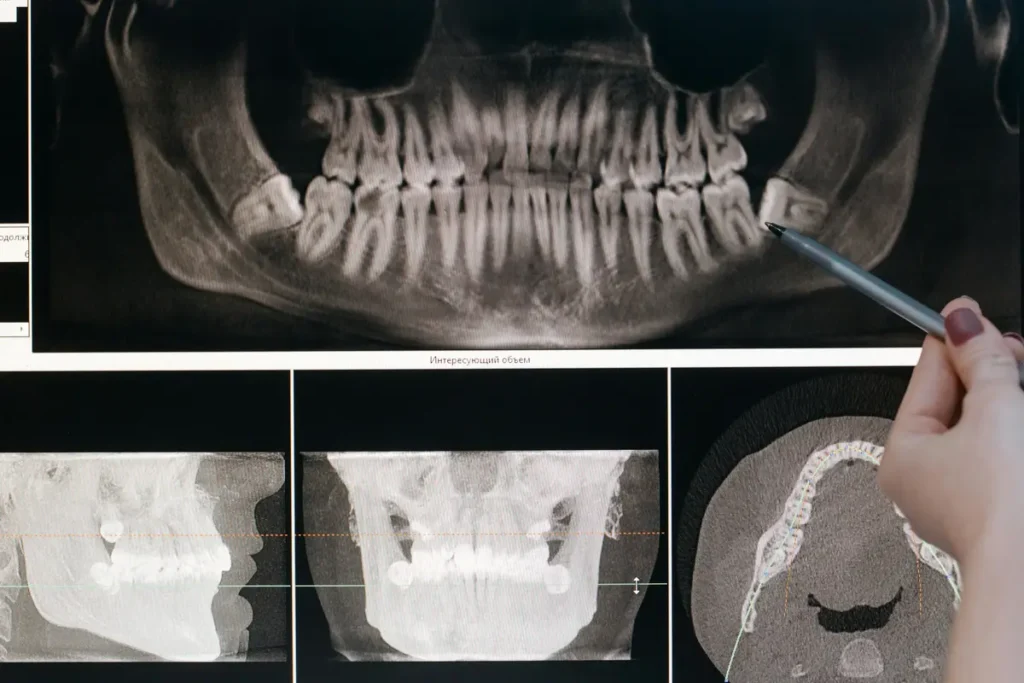

Diagnosi della Carie Secca

Riconoscere una carie secca non è sempre immediato. Molti utenti cercano su Google “come riconoscere una carie” o “carie immagini”, ma spesso queste ricerche portano a diagnosi errate fai-da-te.

Il professionista si avvale di:

- Esame visivo: la carie secca si presenta come una macchia nerastra opaca, spesso nella zona occlusale o interdentale.

- Esplorazione tattile: la superficie della lesione è dura e asciutta, non friabile come nelle carie attive.

- Radiografia bitewing: consente di valutare se la lesione è arrestata o ancora in evoluzione.

- Laser diagnostici o strumenti come DIAGNOdent, che rilevano l’attività della carie.